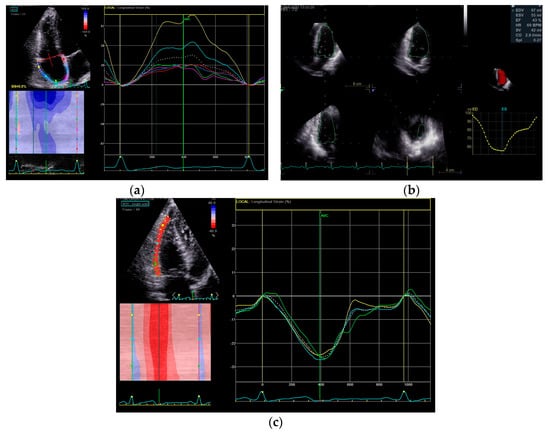

5.1. RV Function Assessment with 3D Echocardiography

5.2. Right Ventricle Speckle Tracking

5.3. Right Atrium Volume and Strain